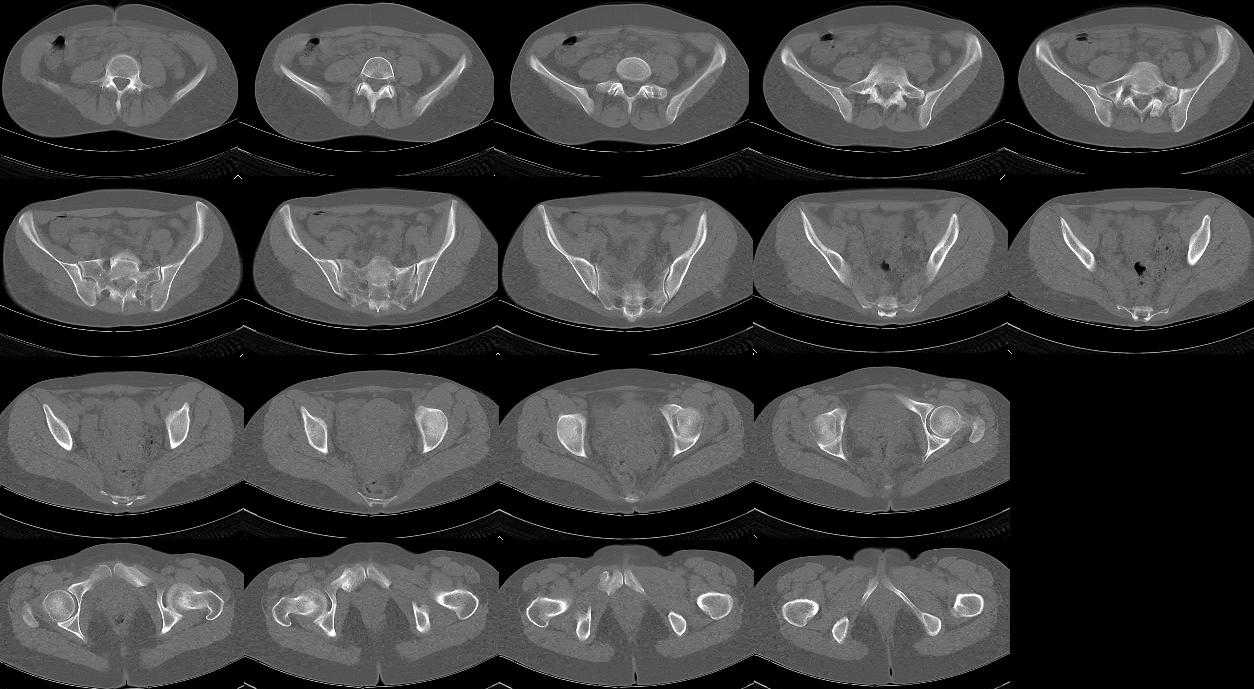

Глубокоуважаемые Сергей и Юрий Алексеевич. благодарю Вас за проявленный интерес с к моей

просьбе. досылаю КТ, фуккциональные Р-граммы пояснично-крестцового отдела позвоночника, фото пациентки.